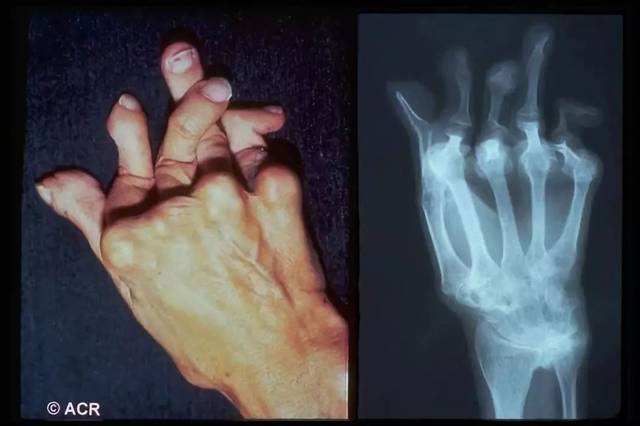

类风湿性关节炎是一种多发性的疾病,这种疾病会对患者带来很大的影响,如今有很多人因为不了解这种疾病的损害,致使本身在呈现这种疾病后没有及时进行医治,致使病况不断恶化。…「查看详情」

类风湿是一种比较难以治愈的疾病,很多人都是患病多年没有找到合适的治疗方法,病情反复,让人十分痛苦。其实类风湿虽然难以治愈,但是治疗的方法是有很多的,找到合适的方法就能很好…「查看详情」

类风湿关节炎是一种很难治愈的慢性疾病,因为此病的疼痛感强烈,所以很多患者四处求医,都在寻找最好的方法治疗类风湿,那么治疗类风湿最好的方法是什么呢?…「查看详情」

类风湿骨关节病之所以成为世界上致残率最高的疾病,除了疾病本身的侵害外,最重要的原因是人们对于类风湿骨关节病缺乏正确的认识和预防常识。那么类风湿关节炎的自我疗法有哪些呢…「查看详情」

正所谓病从细时医。假如你发现自己有类风湿,一定要及时去医院诊治,以控制病情。那么,你知道类风湿的医治方法有哪些吗?…「查看详情」